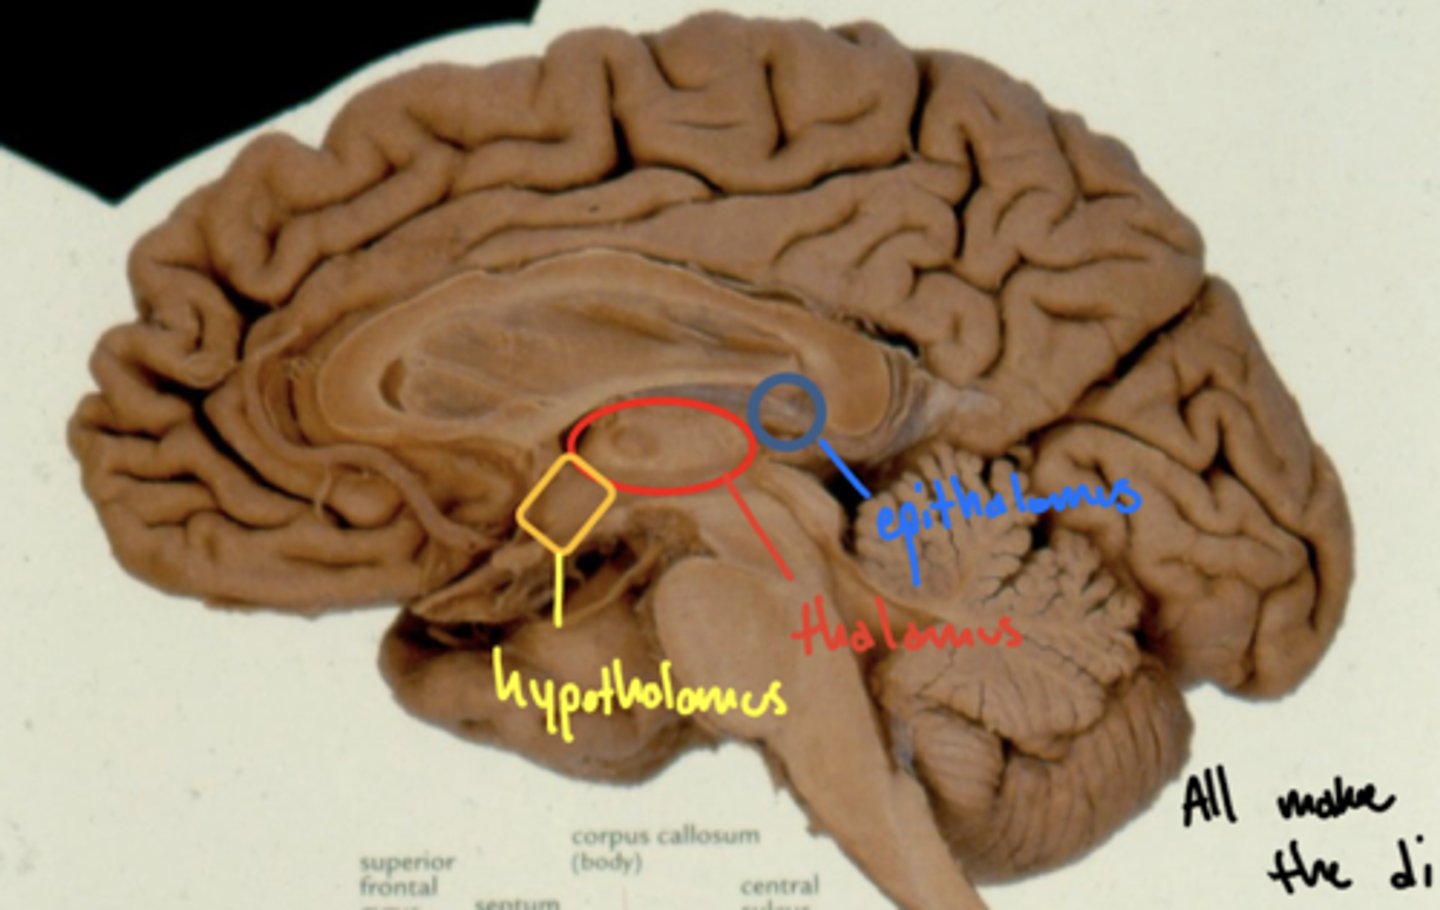

What structures are within the diencephalon?

1. epithalamus

2. thalamus

3. hypothalamus

Where is the hypothalamus in relation to the thalamus?

anteroinferior (in front and below)

Where is the epithalamus in relation to the thalamus?

posterosuperior (behind and above)